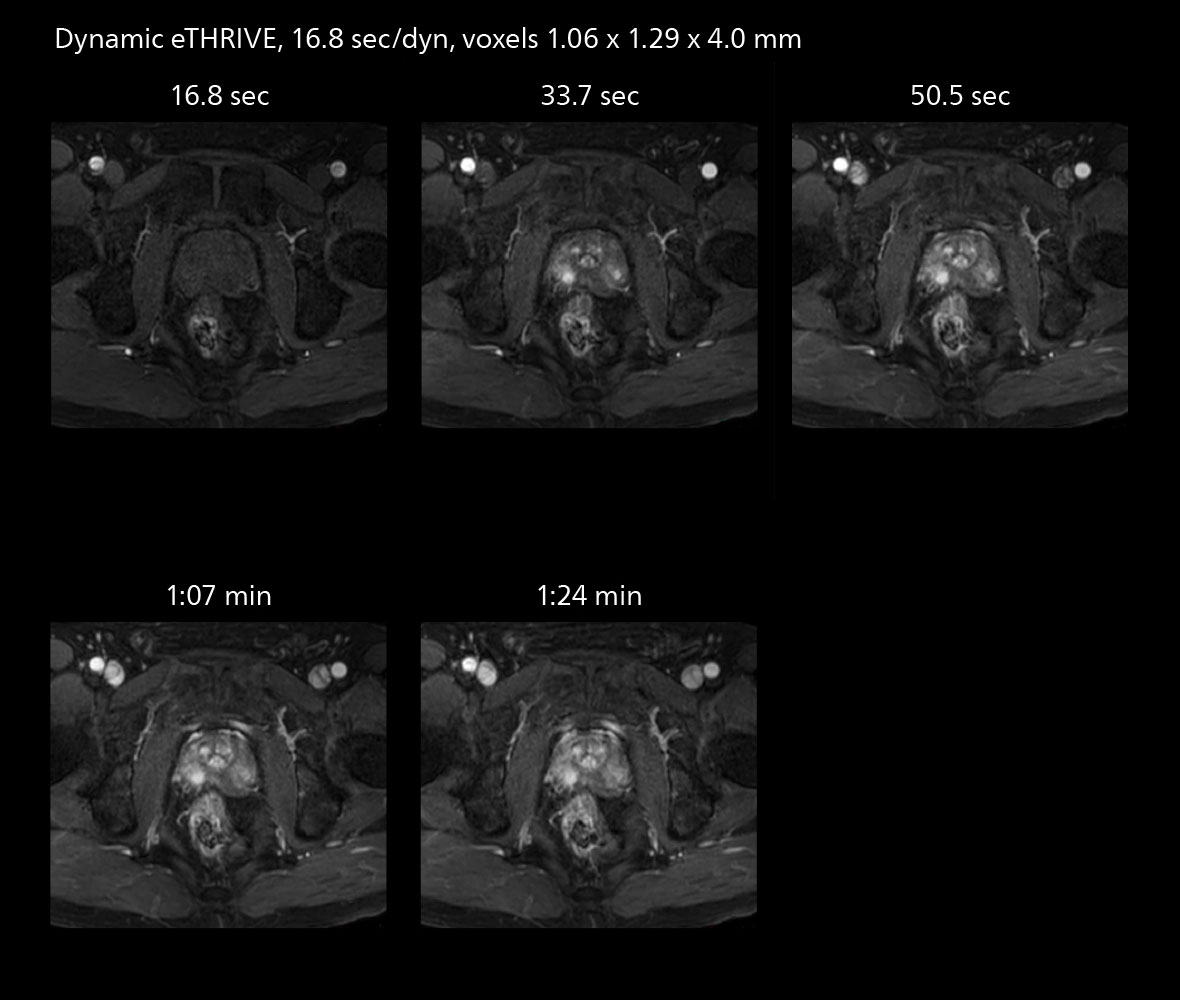

The high performance of the Vega HP gradients is particularly impressive in DWI. “The Vega HP gradients enable us to scan faster and use b-values as high as 2000, for example in prostate DWI and in DWIBS, which provides image quality that is remarkably improved over the previous system and we are able to more easily see lesions.”

Examples of prostate imaging showing faster scan times and improved resolution illustrate the power of SmartPath to Elition X in this case of prostate cancer with PI-RADS score 4.